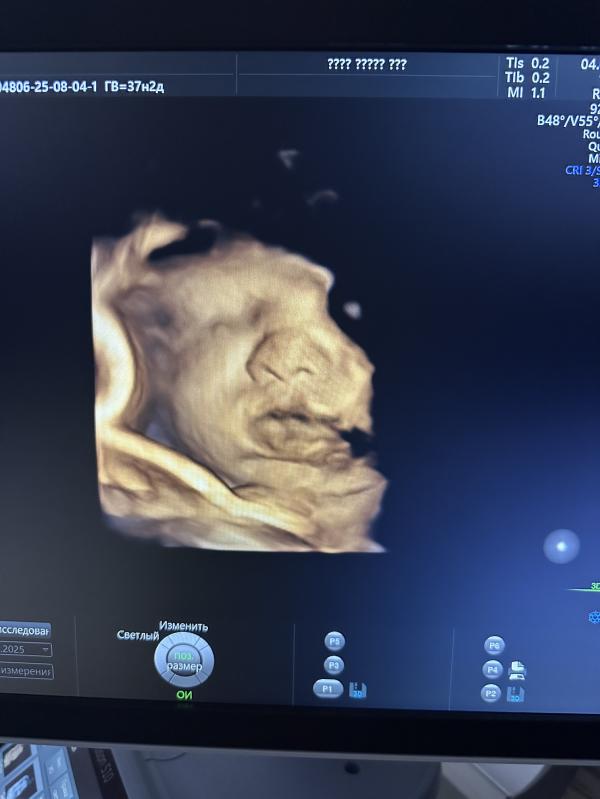

Вот такая губастик 🤗🙈😻

Ага, сегодня в полном восторге 🫣😻 смотрю на эти фото и умиляюсь 😍 Носик мой 🙈 губки папины 😍👌